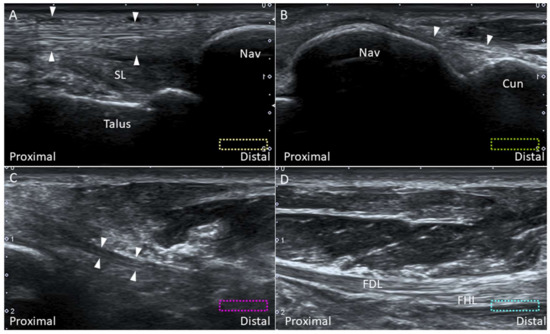

2.8.2. Scanning Technique

2.8.3. Clinical Relevance

2.9.2. Scanning Technique

2.9.3. Clinical Relevance